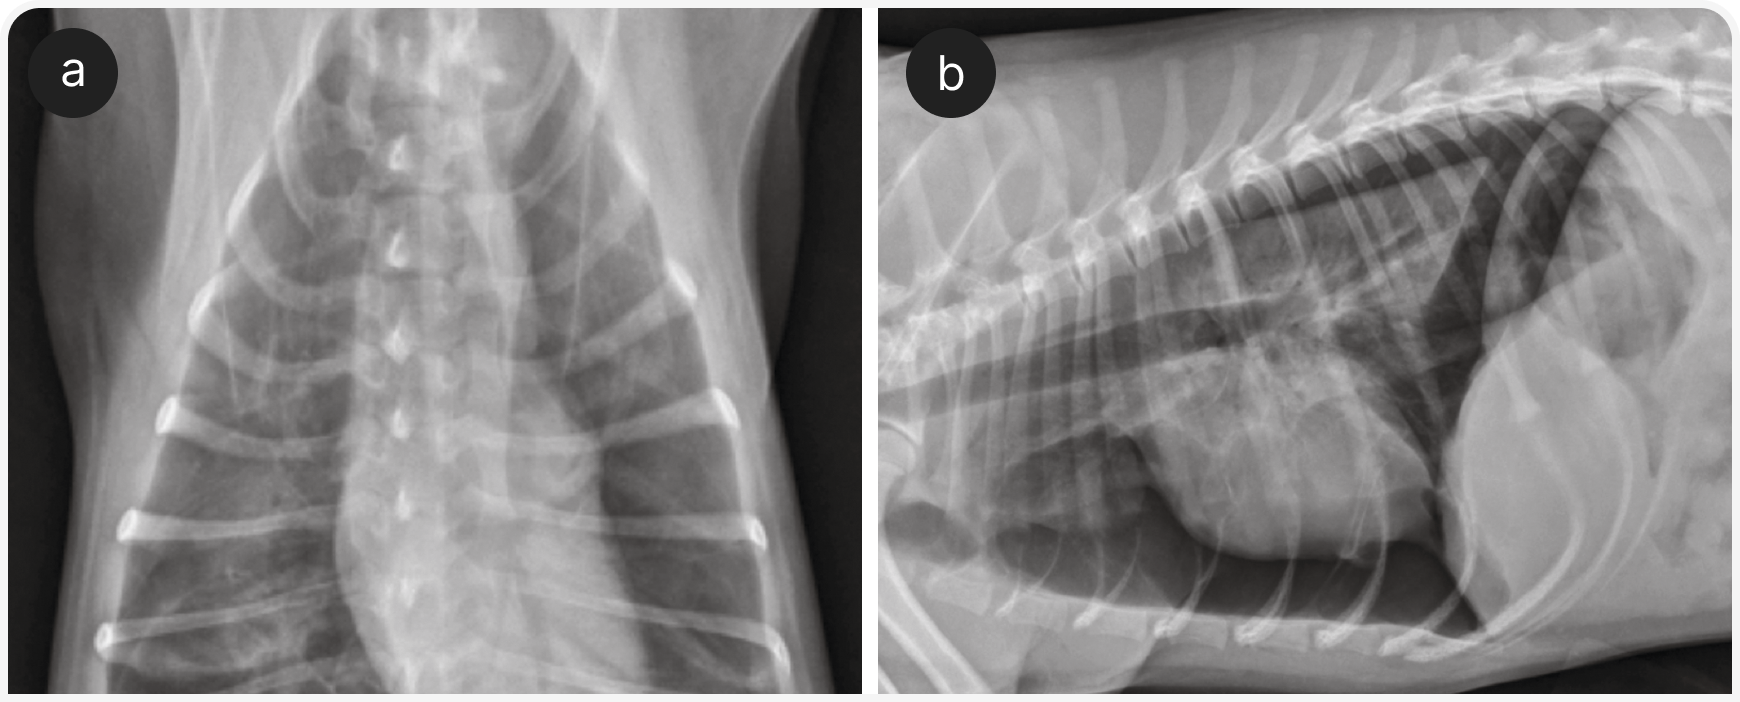

Рентгенография органов грудной клетки — основной метод диагностики у собак с заболеваниями легочной паренхимы (Рисунок 4), так же используется «прикроватное» УЗИ (POCUS), если это возможно, и эхокардиографией, если в списке дифференциальной диагностики высока вероятность заболевания сердца (Рисунок 5). В ожидании первоначального диагностического обследования можно рекомендовать компьютерную томографию органов грудной клетки и эндотрахеальный лаваж. По их результатам решают, следует ли ограничить лечение ингаляцией кислорода или нужно добавить антибиотики, диуретики, стероиды, бронходилататоры.

Для диагностики гемоторакса, транссудата в сравнении с экссудатом или септического выпота рекомендуется определить гематокрит, общее содержание растворенных веществ в плазме крови, содержание глюкозы, лактата, а также провести экспресс-цитологическое исследование выпота. После торакоцентеза показана рентгенография органов грудной клетки для выявления легочной буллы, объемного образования в легких, кардиомегалии или другой причины (Рисунки 6 и 7).

В этих случаях также возможно поражение легких и/или плевральной полости (например, ушибы легких или пневмоторакс), поэтому аускультативная картина изменчива; для выявления некоторых из этих изменений (например, плеврального выпота, отека легких или отсутствия признака скольжения) может быть полезен POCUS. Если проникающее поражение грудной стенки не очевидно сразу, для выявления его симптомов целесообразно провести рентгенографию органов грудной клетки, поскольку его требуется лечить хирургически (Рисунок 8).